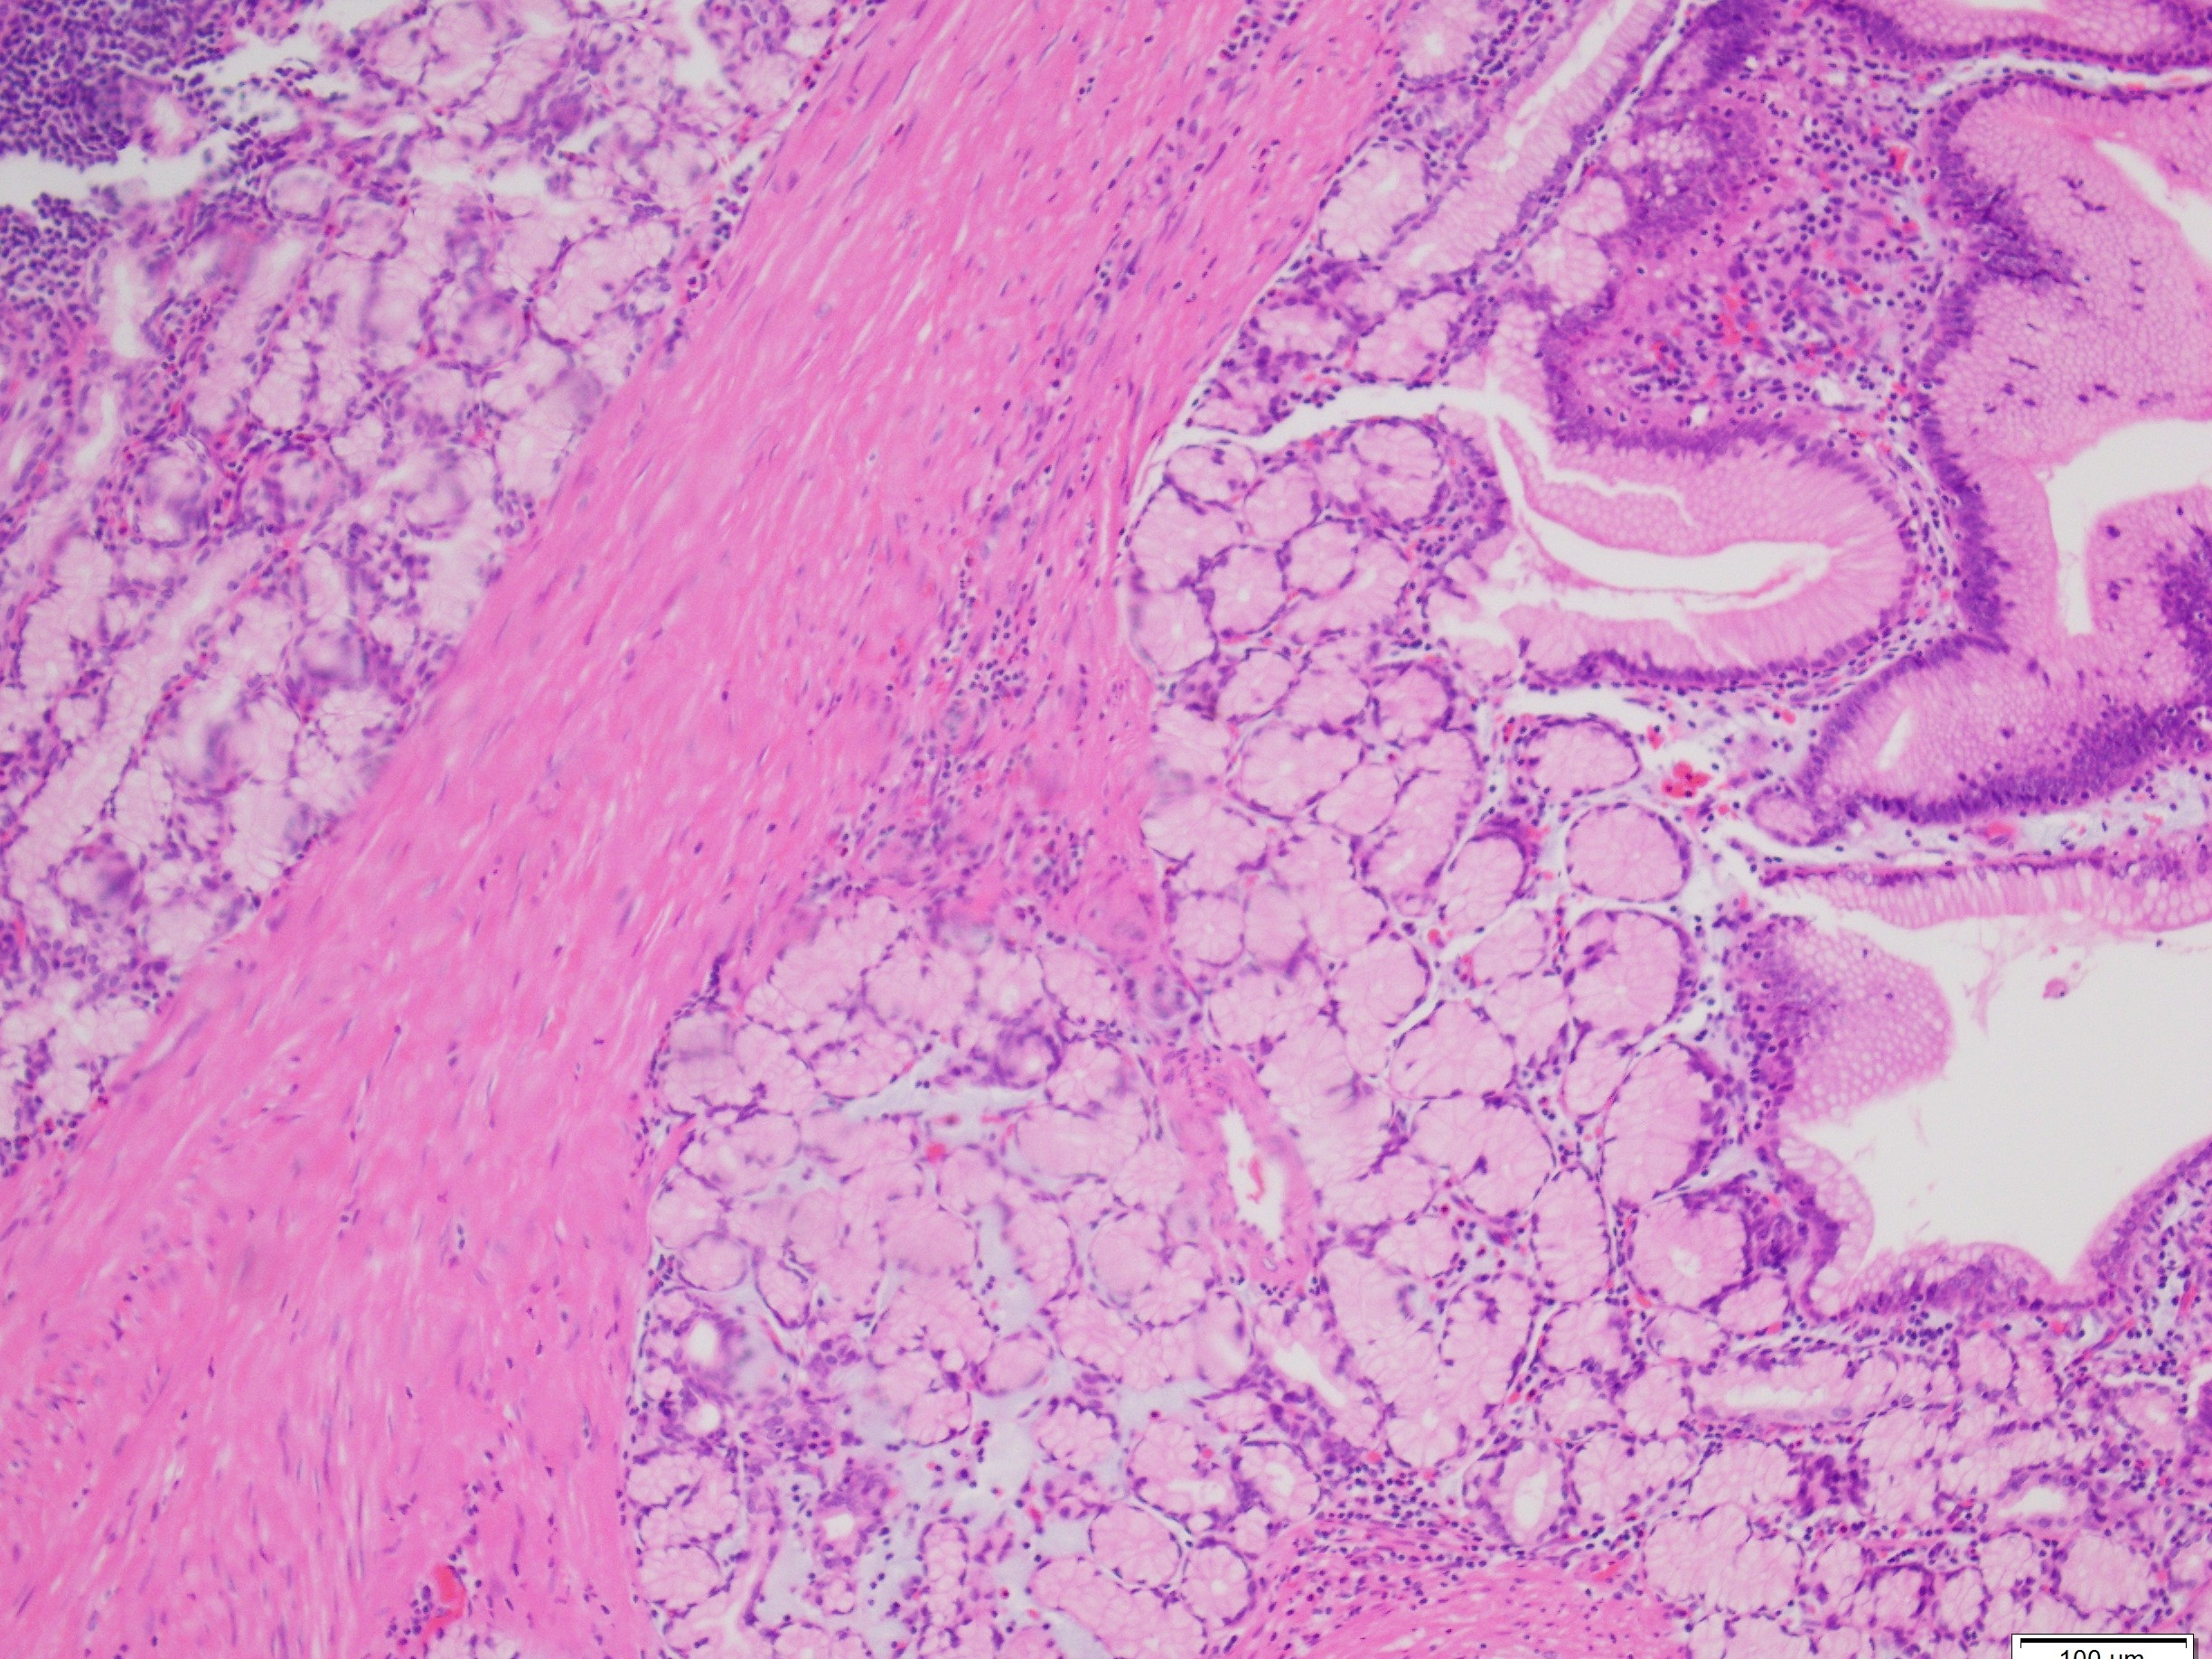

Histologically, PJS polyps are distinctive, showing an arborizing network of smooth muscle originating from the muscularis mucosae (Figures 1 and 3), with fronds of lamina propria and non-dysplastic epithelium (Figures 2-4)—features that can help distinguish them from other polyp types. However, their histologic overlap, particularly hamartomatous polyps and mucosal prolapse polyps, especially in the colon, can occasionally create diagnostic challenges (3,4). One of the most concerning aspects of PJS is its association with a substantially elevated lifetime risk for multiple malignancies. Cumulative cancer risk is estimated between 81%and 93% by age 65. Individuals with PJS are at increased risk for cancers not only of the gastrointestinal tract—such as colorectal, gastric, pancreatic, and small bowel—but also of the breast, ovary, cervix (adenoma malignum), and testes (Sertoli cell tumors). For example, the relative risk of pancreatic cancer may be over 100-fold higher than in the general population (1,2).